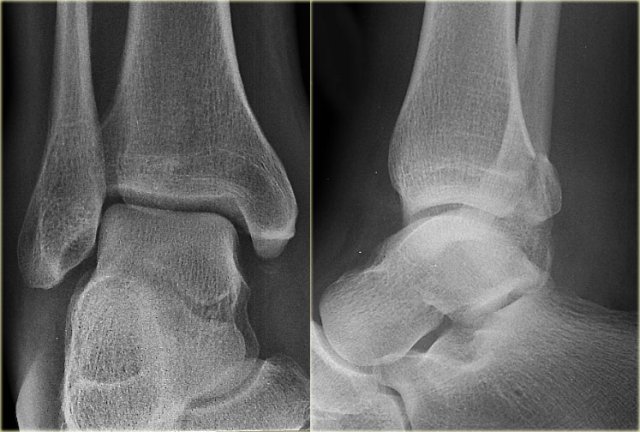

The images show an obvious Weber B fracture.

On the AP-view the linear lucency is the clue to a tertius fracture (red arrow).

It results from subtle malalignment of the fracture fragment.

Likewise in some cases malalignment can result in a linear density.

Trimalleolar Weber B fracture Trimalleolar Weber B fracture

In this case there is a Weber B fracture with avulsion of the medial malleolus.

The bright line on the AP-view indicates a large tertius fracture fragment.

This tertius fracture can also be seen on the lateral view, but in many cases we need all the information of both the lateral and AP-view to diagnose a tertius fracture.